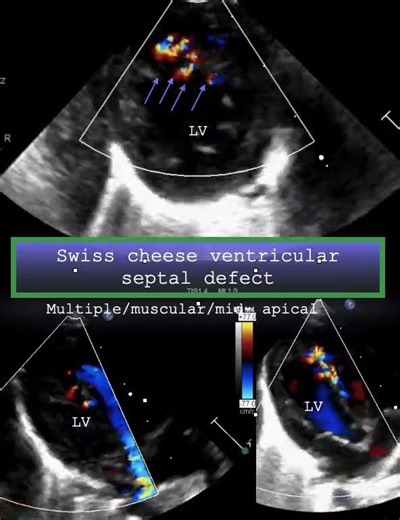

Echo - Ventricular

Echocardiogram - VSD

in Echo - VSD